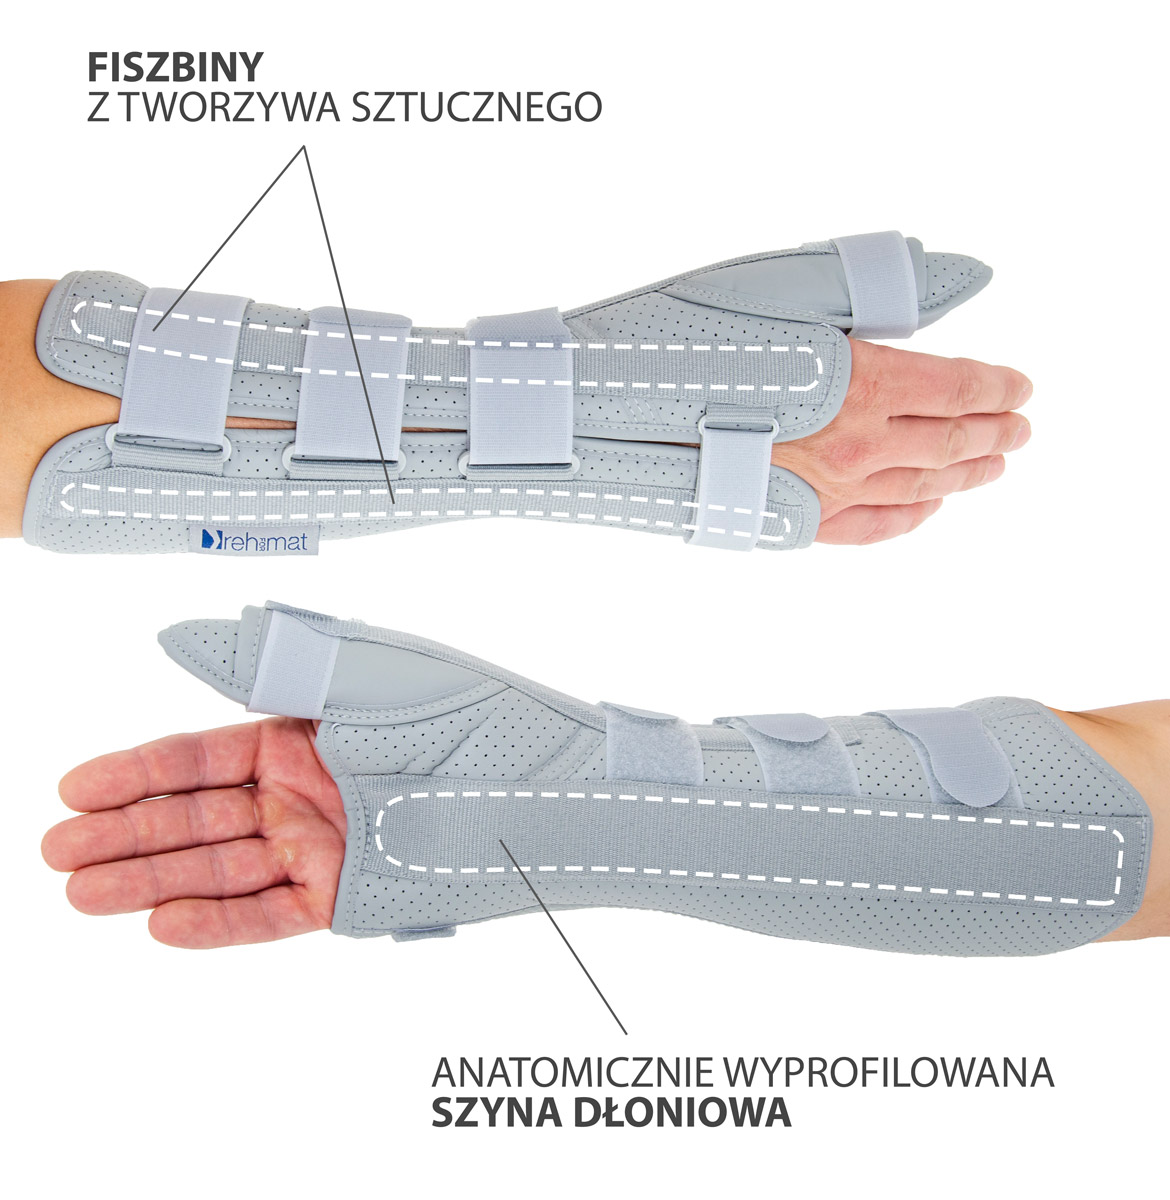

Otwarta orteza przedramienia została wykonana według nowego bardziej anatomicznego kształtu, dzięki czemu lepiej stabilizuje staw promieniowo-nadgarstkowy, nadgarstek i przedramię. Wyrób posiada konstrukcję otwartą, co ułatwia jego zakładanie na kończynę oraz regulowane zapięcie przednie, co czyni ortezę jeszcze bardziej uniwersalną i ułatwia dopasowanie do każdego kształtu dłoni. W górnej części wyrobu zainstalowano dwie fiszbiny ortopedyczne, które wraz z łyżką dłoniową przekrojowo tworzą trzy obwodowe punkty podparcia kończyny górnej. Taki sposób stabilizacji przedramienia jest sposobem najbardziej skutecznym. Zapięcia wyrobu wykonano przy użyciu zespołu dwóch szerokich taśm obwodowych oraz jednej wąskiej taśmy dłoniowej. Zakres regulacji zapięć jest bardzo duży i dzięki temu gwarantuje on szeroki zakres regulacji i stabilizacji.

W dłoniowej części ortezy zainstalowano miękką elastyczną poduszkę poprawiającą komfort użytkowania wyrobu. Konstrukcja ortezy oraz użyte surowce przeciwdziałają wystąpieniu u jej użytkowników zespołu cieśni nadgarstka.

Dodatkowo w wyrobie zainstalowano aluminiową szynę boczną ze stabilizatorem, której zadaniem jest funkcja odwiedzenia kciuka. Zakres i sposób jego odwiedzenia może być dowolnie kształtowany przez odpowiednie przegięcie szyny.

- Doskonała stabilizacja – dzięki zastosowaniu trzech usztywnień rozmieszczonych na obwodzie wyrobu, uzyskano doskonałą jego stabilizację.